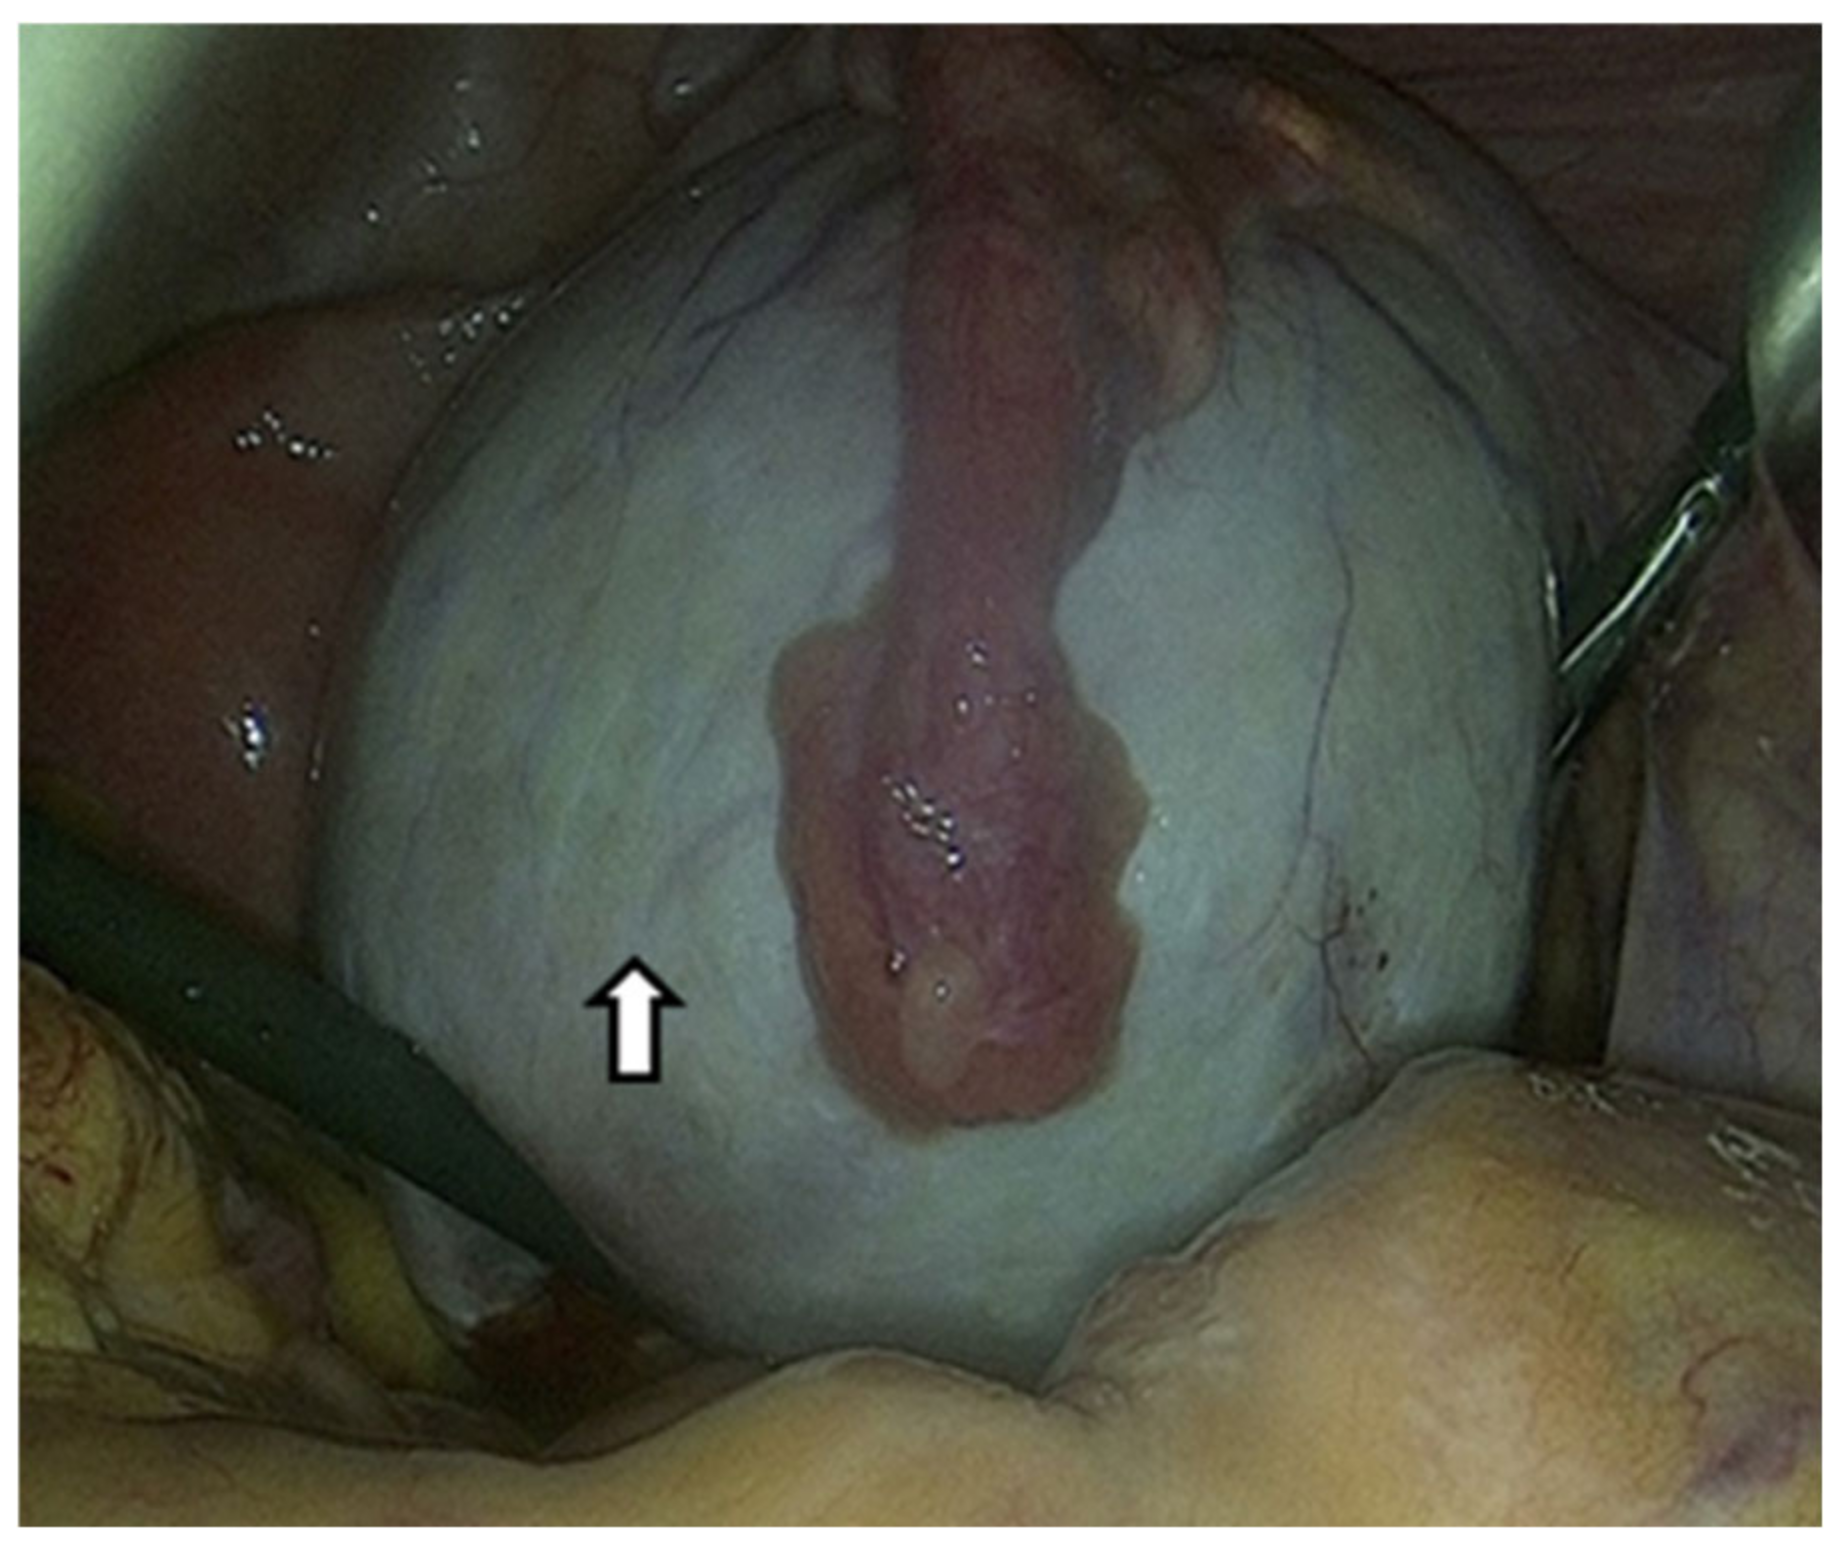

6.1.4. Laparoscoy